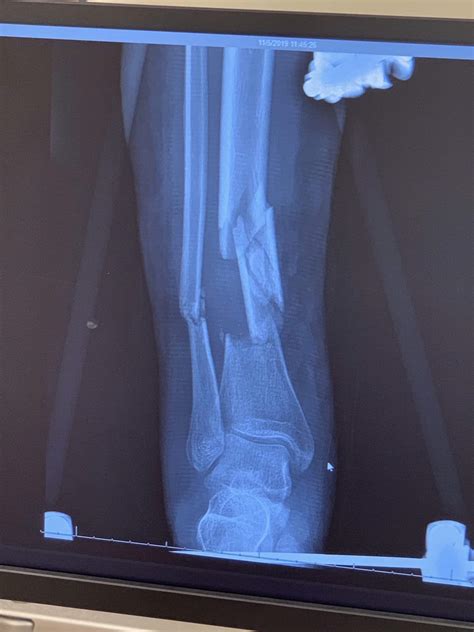

• Imaging Tests: X-rays are the primary imaging tool used to diagnose bone fractures. They can provide clear images of the bone structure, allowing the healthcare provider to determine the type and extent of the fracture. In some cases, additional imaging tests such as CT scans or MRI may be required for a more detailed assessment.